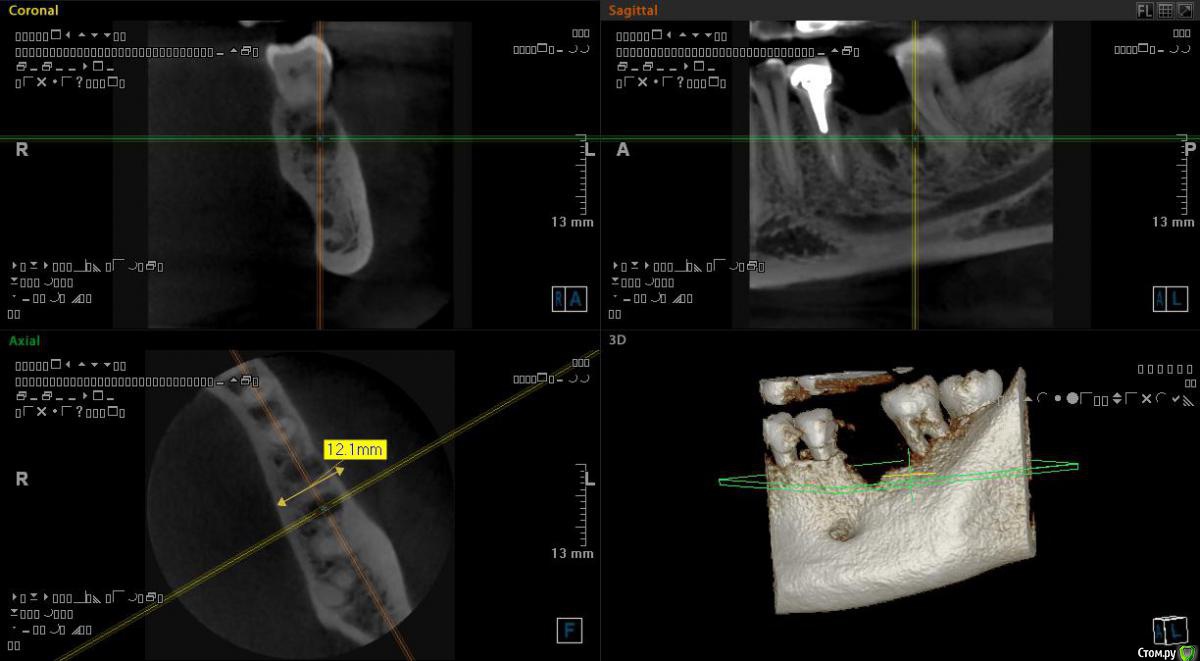

Самарец Опубликовано 11 августа, 2020 Автор Поделиться Опубликовано 11 августа, 2020 срезы выставлены не корректно, покажите еще, в том числе в области седьмого зубаСпасибо за ответ. Так пойдёт? Ссылка на комментарий

Irouil Опубликовано 11 августа, 2020 Поделиться Опубликовано 11 августа, 2020 Все в порядке 1 Ссылка на комментарий

Самарец Опубликовано 11 августа, 2020 Автор Поделиться Опубликовано 11 августа, 2020 Все в порядкеСПАСИБО БОЛЬШОЕ!!!!!!! 1 Ссылка на комментарий